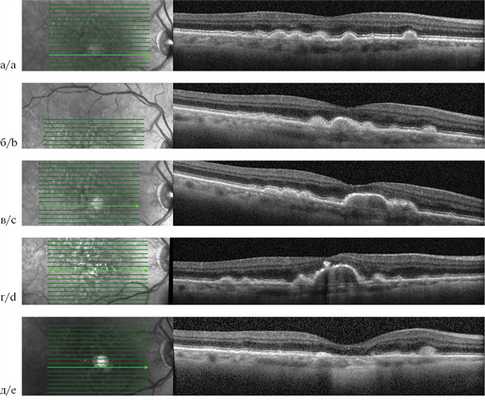

Начальный этап развития ОРПЭС характеризуется аккумуляцией друзеноидного материала между РПЭ и мембраной Бруха. Напряжение кислорода снижается на 30—50% у вершины в зависимости от роста друзеноидной ОРПЭС. Клетки РПЭ, лежащие на верхушке друзы, максимально удалены от хориокапилляров и могут мигрировать в поисках кислорода из капилляров сетчатки. Оставшиеся клетки РПЭ подвержены апоптозу, разрушению с переходом органелл клетки в состав друз [8]. Последующая фаза — регрессия, протекает с прогрессированием атрофии наружных слоев сетчатки по мере уменьшения количества клеток РПЭ на поверхности ОРПЭС. Процесс образования друзеноидного материала заканчивается, происходит «самоочищение» последнего, объем ОРПЭС уменьшается, и в конечном итоге наблюдается коллапс друзеноидной ОРПЭС, на месте которой регистрируется зона полной атрофии РПЭ и наружных слоев сетчатки (географическая атрофия). По мнению J. Sarks и соавторов, по мере увеличения как мягких сливных друз, так и друзеноидной ОРПЭС материал внутри них распадается и становится более тонким по своей природе, что приводит к более быстрому коллапсу друзы и развитию географической атрофии [9]. На ОКТ при этом можно наблюдать негомогенный характер друзеноидного материала с появлением гипорефлективных участков. Даже до явного развития географической атрофии ОРПЭС приводит к дисфункции фоторецепторов и последующей наружной атрофии сетчатки. Для друзеноидных ОРПЭС, выявленных на раннем этапе развития, характерна высокая острота зрения. Развитие наружной атрофии сетчатки в процессе существования ОРПЭС может объяснять потерю 15 и более букв в 26% случаев в отсутствие прогрессирования до поздней стадии ВМД (по классификации AREDS). При офтальмоскопии обнаружено, что при развитии гипопигментации риск снижения остроты зрения удваивается [7, 9] (рис. 2).

Рис. 2. Оптическая когерентная томограмма пациента с возрастной макулярной дегенерацией.

Жизненный цикл друзеноидной отслойки ретинального пигментного эпителия сетчатки от мягких друз до географической атрофии: а — 2013 г.; б — 2014 г.; в — 2015 г.; г — 2017 г.; д — 2018 г.